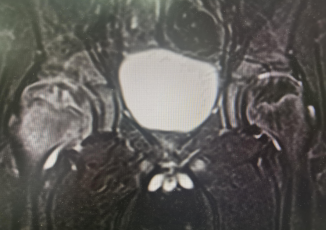

术前MRI

“股骨头缺血坏死”这种疾病一般发现确诊时就要诊治,症状表现为髋关节压痛明显,被动内旋时疼痛明显,X线的变化主要是干骺端、骺板及髋臼的改变,可能发现股骨头变形,核磁共振对于股骨头内、外侧显影更为清晰。治疗方式早期一般有卧床休息、牵引治疗、双下肢内旋位管型石膏固定,后期为恢复股骨头血供,使股骨头形态发育正常,可选择股骨头钻孔引流、髂腰肌松解术来治疗。

王泺镔主治医师介绍,来院就诊的这几个小朋友都是股骨头缺血坏死,这是一种常见于2-12岁(6-8岁为发病高峰)的一种疾病,不少患儿因症状轻微而未就诊。患儿常有跛行,有时诉髋部、膝部或大腿疼痛。检查发现患髋活动受限(特别是外展和内旋受限)以及大腿肌肉轻度萎缩。此种疾病最主要的影响就是对平时走路的影响,会导致髋外旋和内旋明显,屈髋时下肢有被迫性外旋的动作,股骨头被破坏。